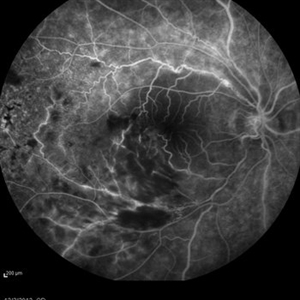

Behcet's Disease Behcet's DiseaseMar 13 2013 by Hamid Ahmadieh, MD Early phase FA of the right eye of a 23-year-old man with retinal vasculitis and branch retinal vein occlusion (BRVO) due to Behcet's disease . Photographer: Solmaz Shahmohammad, Negah Eye Center, Tehran Imaging device: Heidelberg Spectralis Condition/keywords: branch retinal vein occlusion (BRVO), retinal vasculitis

Behcet's Disease Behcet's DiseaseMar 13 2013 by Hamid Ahmadieh, MD Mid phase FA of the right eye of a 23-year-old man with retinal vasculitis and branch retinal vein occlusion (BRVO) due to Behcet's disease . Photographer: Solmaz Shahmohammad, Negah Eye Center, Tehran Imaging device: Heidelberg Spectralis Condition/keywords: branch retinal vein occlusion (BRVO), retinal vasculitis

Behcet's Disease Behcet's DiseaseMar 13 2013 by Hamid Ahmadieh, MD Late phase FA of the right eye of a 23-year-old man with retinal vasculitis and branch retinal vein occlusion (BRVO) due to Behcet's disease . Photographer: Solmaz Shahmohammad, Negah Eye Center, Tehran Imaging device: Heidelberg Spectralis Condition/keywords: branch retinal vein occlusion (BRVO), retinal vasculitis

Behcet's Disease Behcet's DiseaseMar 13 2013 by Hamid Ahmadieh, MD Wide field FA of the right eye of a 23-year-old man with retinal vasculitis and branch retinal vein occlusion (BRVO) due to Behcet's disease . Photographer: Solmaz Shahmohammad, Negah Eye Center, Tehran Imaging device: Heidelberg Spectralis Condition/keywords: branch retinal vein occlusion (BRVO), retinal vasculitis